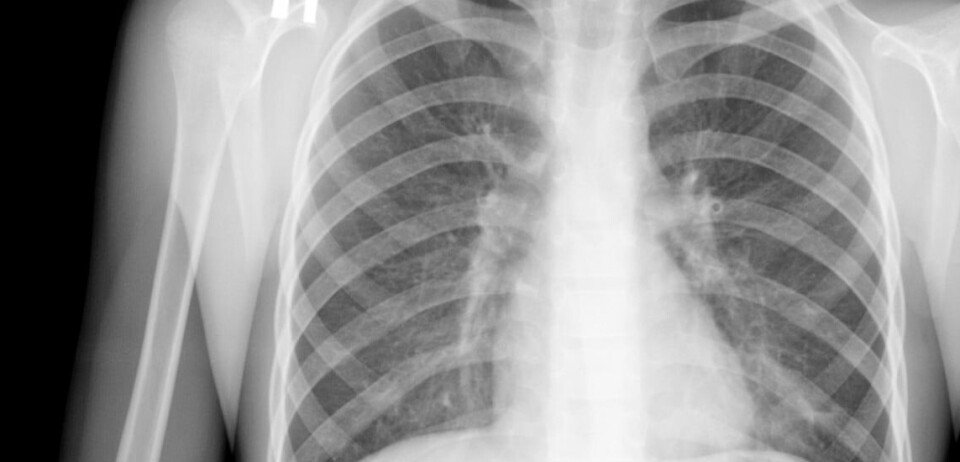

Sjansen for å overleve lungekreft i Danmark stiger

Flere enn før er fortsatt i live ett år etter å ha fått lungekreftdiagnose i Danmark.